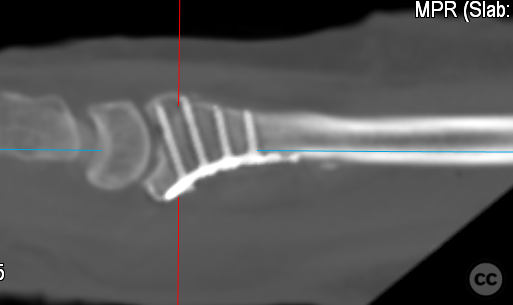

Multifragmentary Distal Radius Fracture with Flipped Ulnar Articular Margin

Clinical Details

Clinical and radiological findings:  A 72-year-old female sustained a multifragmentary, dorsally displaced distal radius fracture after a fall down stairs. Initial reduction revealed a 180-degree flipped fragment of the volar ulnar articular margin, unreducible by closed means. There was no mention of associated neurovascular compromise or open injury. Radiographs and intraoperative fluoroscopy confirmed the presence of a multifragmentary intra-articular fracture (AO/OTA 23-C3), with a flipped volar ulnar fragment and radial styloid impaction. The distal radioulnar joint alignment was restored postoperatively.